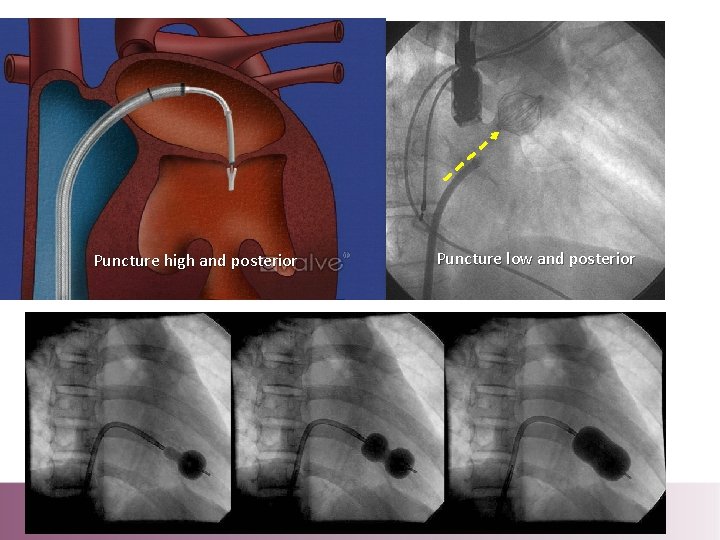

Puncture high and posterior Puncture low and posterior